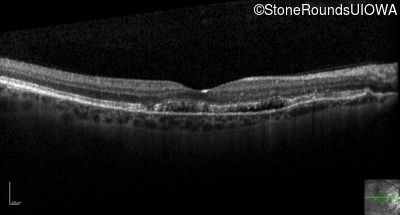

Optical Coherence Tomography - Right - 20/40

Exemplar / OCT Stack